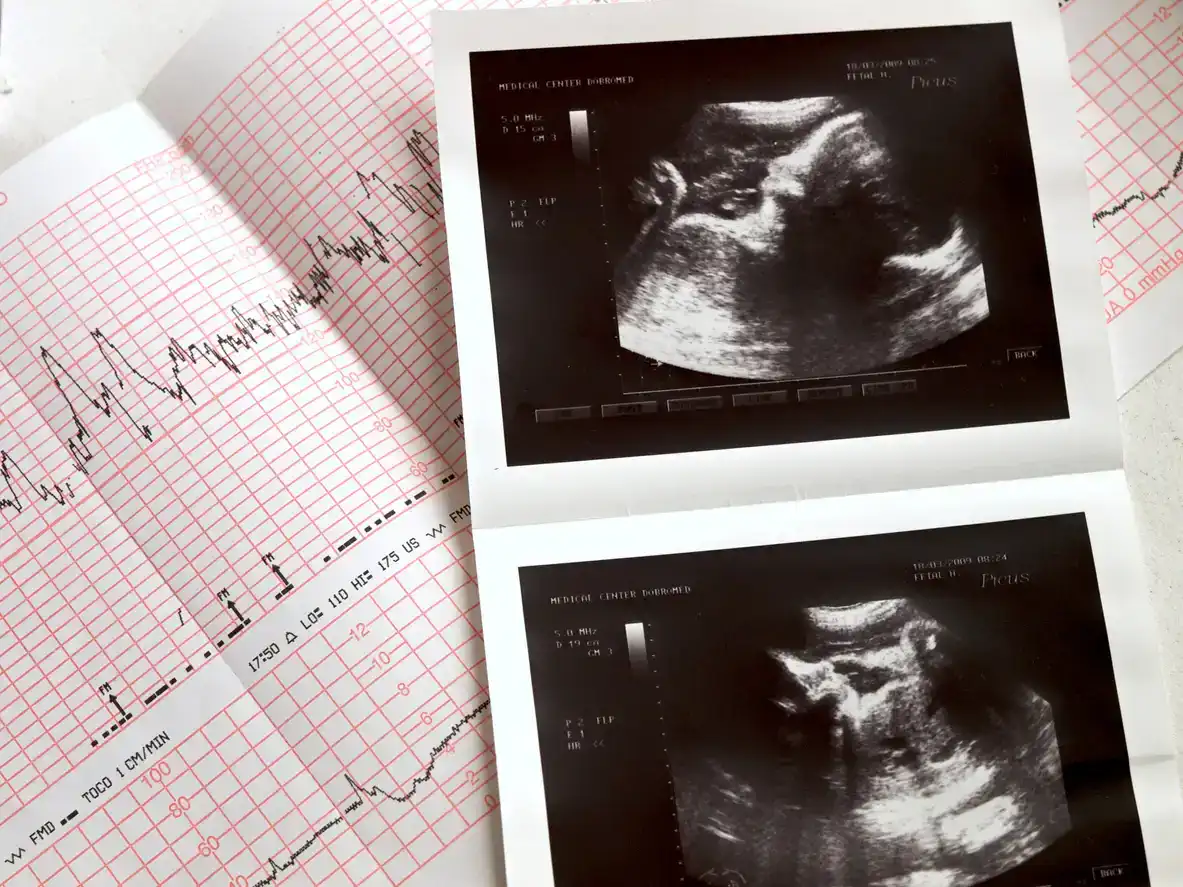

Os médicos podem usar ultrassom transvaginal para detectar os batimentos cardíacos fetais entre a quinta e meia a seis semanas de gravidez (Chertoff, 2018).

O primeiro exame de ultrassom é mais frequentemente realizado na 7ª ou 8ª semana de gravidez, durante o exame da vagina ou da cavidade abdominal. Outros médicos podem esperar 11–14 semanas porque a condição do bebê pode afetar a precisão da medição (Field, 2023).

Ultrassom Doppler, que usa ondas sonoras de alta frequência refletidas nos glóbulos vermelhos para medir o fluxo sanguíneo. A ultrassonografia Doppler é um pouco diferente da ultrassonografia tradicional. Isso ocorre porque o ultrassom tradicional tira fotos, mas não consegue detectar o fluxo sanguíneo (CHIPS).

O Doppler fetal, também chamado de ecocardiografia fetal, utiliza um instrumento fora do corpo para examinar o feto. É indolor e não invasivo.